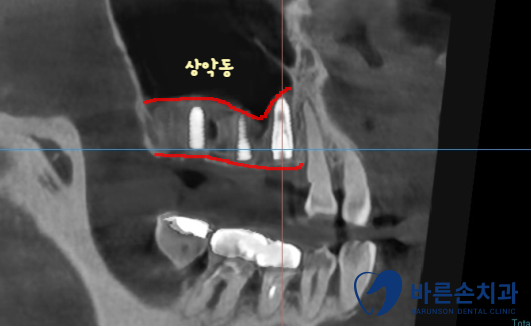

치료가 다 끝난 사진입니다!

임플란트도 뼈 안에 가지런히 잘 식립되어있습니다.

상실되어있던 치아들이 전부 생기게 되었고

치아색 보철로 내 치아처럼 자연스럽게 제작되었습니다

이제 아래 치아와 전부 맞닿게 되니까

식사 하시기 훨씬 편해지실겁니다!